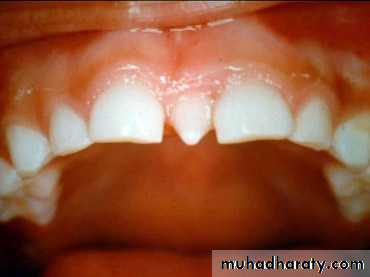

1- Crowding2-Midline diastema

Abnormal labial Frenum If the frenum is thick, itprevents the closure of diastema (which is normal during mixed dentition prior to the eruption of canines)In these cases a frenectomy is indicated11-TRANSPOSITION:- An abnormality where the position of teeth is interchanged- The most transposed teeth: The maxillary canines & first premolars